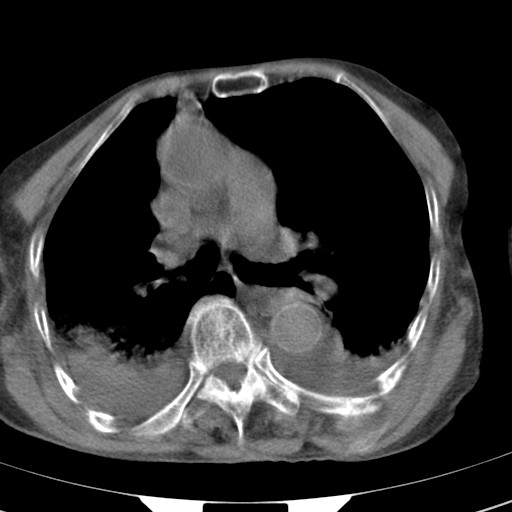

标题: CT21467:女,93岁,摔伤后检查。

女,93岁,摔伤后检查。

右肺炎症,心功能不全伴双侧胸腔积液,右下肺膨胀不全,食管裂孔疝,冠脉钙化,心包少量积液,左侧肋骨骨折,请上传骨窗.

创伤性湿肺,双侧胸腔积液。可能有食管裂孔疝,进一步检查。骨折有无根据自己的机器及片子再仔细看吧。

右侧锁骨\\肩胛骨骨折、右侧湿肺,心功能不全伴双侧胸腔积液,右下肺膨胀不全,左膈破裂或食管裂孔疝,冠脉钙化,心包少量积液,请上传骨窗.

右肺炎症,心功能不全伴双侧胸腔积液,右下肺膨胀不全,食管裂孔疝,冠脉钙化,心包少量积液,左侧肋骨骨折,右肩甲骨粉碎性骨折。93岁,高寿哇!

右肺炎症,心功能不全伴双侧胸腔积液,右下肺膨胀不全,食管裂孔疝,冠脉钙化,心包少量积液,左侧肋骨骨折,右肩甲骨粉碎性骨折。